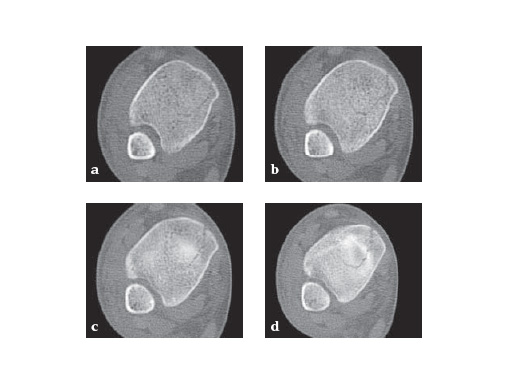

The LCP Medial Distal Tibia (LCP MDT) has a lower profile distally which is optimal for the medial side of the distal tibia where there is often little soft-tissue coverage. Since certain fracture patterns require more distal screw options, the LCP MDT has three diverging distal screws above the joint that capture the anterior and posterior fragments and place the plate more distally. The 3 distal locking head screws diverge across the subchondral bone. The distal locking holes accept 3.5 mm locking head screws, 2.7, 3.5 and 4.0 mm cortex screws.

Additionally, 2 combination holes were added distally in the head of the plate to allow placement of cancellous and cortex screws. These 2 combination holes distally accept 3.5 mm locking head, 3.5 mm or 4.0 mm cortex, or 4.0 mm cancellous bone screws. The distal K-wire hole accepts a 1.6 mm K-wire.

The plate shaft has been widened to 13.5 mm, which is comparable to a narrow LC-DCP 4.5. At the proximal end of the plate, an articulated tension device (ATD) hole was added to allow for compression and distraction

using the articulated tensioning device.

29-year-old female after a motor vehicel crash

Case provided by Sean Nork, Washington, USA

The fibula was reduced and stabilized through a posterolateral surgical approach. A small anterior incision was used to apply multiple clamps and to access the fracture reduction. A medial locked distal tibial plate was placed adjacent to the anteromedial surface of the tibia through a 4 cm distal incision. Multiple proximal screws were placed through small incisions overlying the plate.